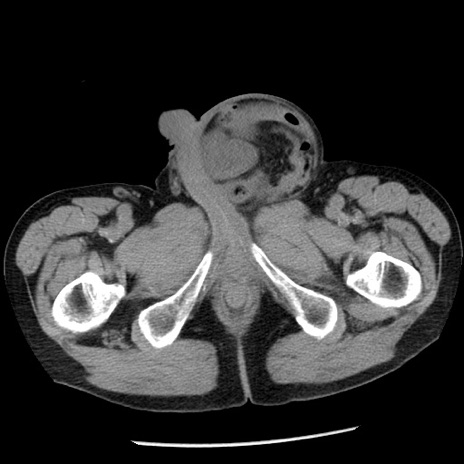

症例26(横断像)

【症例】80歳代男性

【主訴】嘔吐

【現病歴】昨晩2回嘔吐あり、今朝になっても嘔吐あり。来院。

【既往歴】胃潰瘍

【身体所見】意識清明、BT 37.6℃、BP 166/95mmHg、HR 100bpm、SpO2 97%、腹部:平坦・軟、腸蠕動音聴取良好、圧痛なし。

【データ】WBC 21900、CRP 1.46